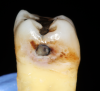

Fig 5. Removing firm affected dentin.

Figure 5

To determine how much to remove, it is important to understand the difference between infected dentin and affected dentin. The infected layer of dentin is highly demineralized, is physiologically unable to remineralize, and contains irreversibly denatured collagen fibrils with a virtual disappearance of cross-linkages.18 It contains bacteria and degraded collagen that cannot be remineralized. On the other hand, the affected dentin has a minimal concentration of bacteria, and the collagen network is still viable.19 Clinically, affected and infected dentin are differentiated by their hardness. Infected dentin is soft and can be easily removed with a spoon excavator (Figure 4). Affected dentin is leathery and requires firm pressure to be removed with a spoon excavator (Figure 5).20